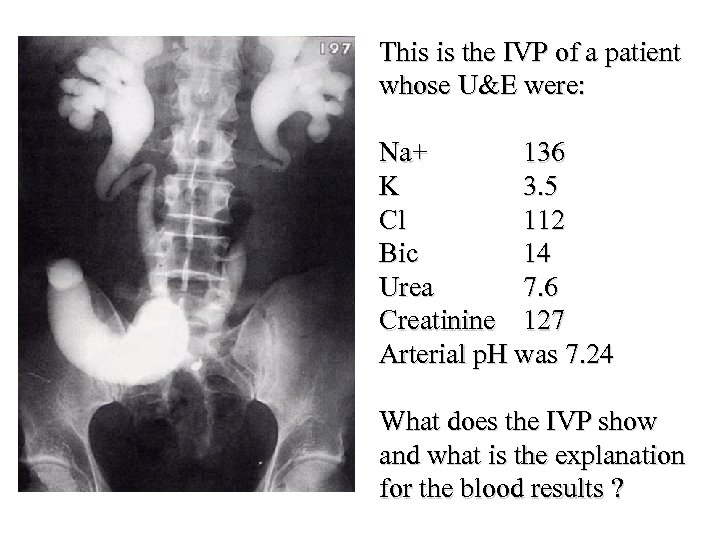

4. A 29 -year-old woman presents with weakness and is found to have a serum potassium of 2. 2 mmol/l and p. H 7. 1. Which of the following would be most suggestive of proximal renal tubular acidosis (RTA type 2)? • • • A B C D E Renal calculi Osteomalacia Serum bicarbonate 8 mmol/l Urinary p. H 6. 5 History of Sjogren’s syndrome

4. A 29 -year-old woman presents with weakness and is found to have a serum potassium of 2. 2 mmol/l and p. H 7. 1. Which of the following would be most suggestive of proximal renal tubular acidosis (RTA type 2)? • • • A B C D E Renal calculi Osteomalacia Serum bicarbonate 8 mmol/l Urinary p. H 6. 5 History of Sjogren’s syndrome

4. A 29 -year-old woman presents with weakness and is found to have a serum potassium of 2. 2 mmol/l and p. H 7. 1. Which of the following would be most suggestive of proximal renal tubular acidosis (RTA type 2)? • • • A B C D E Renal calculi Osteomalacia Serum bicarbonate 8 mmol/l Urinary p. H 6. 5 History of Sjogren’s syndrome

4. A 29 -year-old woman presents with weakness and is found to have a serum potassium of 2. 2 mmol/l and p. H 7. 1. Which of the following would be most suggestive of proximal renal tubular acidosis (RTA type 2)? • • • A B C D E Renal calculi Osteomalacia Serum bicarbonate 8 mmol/l Urinary p. H 6. 5 History of Sjogren’s syndrome